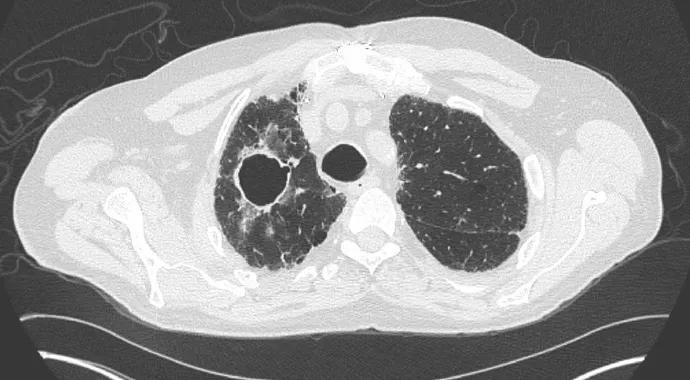

A 66-year-old man had a history of GPA that originally presented with sinus disease, alveolar hemorrhage, pauciimmune crescentic glomerulonephritis and a positive myeloperoxidase antineutrophil cytoplasmic antibody (ANCA). While on maintenance azathioprine, he developed a harsh productive cough with a new cavitary lung lesion without evidence of active disease involving other organs (Figure 3). A sputum culture grew Mycobacterium avium complex (MAC), and the patient was started on antimicrobials. Despite this treatment, the lesion worsened. Bronchoscopy was negative for MAC or other infection with an unremarkable cytologic examination. A thoracoscopic biopsy revealed a poorly differentiated non-small-cell lung carcinoma.

View image online (https://assets.clevelandclinic.org/transform/df7dd77a-61ab-4c0f-9a78-354939e626f5/Langford-fig3_jpg)

Figure 3.